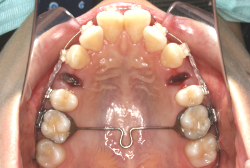

成長発育期の上顎前突症例・非抜歯治療

診断の結果、典型的なアングル2級1類の上顎前突です。上下歯列の正中の不一致も見られます。しかし、歯の大きさは平均値に近く、配列の凸凹がそれほど見られません。このまま放置すると、将来的には抜歯を伴う矯正治療を行う可能性が高くなりますが、このタイミングで適切な治療をすると、非抜歯治療が可能かもしれません。

矯正歯科医が着目するのは、奥歯の噛み合わせの位置関係です。前歯の位置にそれなりの差が生じていても、奥歯の位置が正しければそれほど重症という評価にはなりません。このケースの場合は、上下の第一大臼歯の位置関係は、直線的に一致しているタイプでした(矢印が一致)。混合歯列時期の奥歯の位置関係としては、ほぼ正常な状態といえますが、症状から言うと、上の奥歯をもっと後ろに下げてやることができれば、上顎歯列全体に余裕ができるので、凸凹も解消できるし、前歯の傾きを内向きに修正することもできると考えられました。しかしこのまま全体に永久歯が生えきってしまうと、上の前歯が出たままになってしまいますので、生え替わりが完了する前に大急ぎで奥歯を後ろに下げる必要があると判断しました。

こういう症状でもっとも効果があるのが、顎外固定装置と言って、お口の外部から奥歯に力をかける方法です。 写真の装置はネックバンドというタイプの装置です。この装置は取り外し式ですので、夜寝るときに毎日自分で取り付けて、寝ている間に少しずつ上の奥歯を後ろに下げていきます。この装置には、奥歯を後ろに下げる効果だけでなく、上顎の過剰な成長発育の抑制、下顎の成長促進作用があるとされており、上顎前突の症状にはいずれも有利な効果が期待できます。

ネックバンドを1年半使用して、上顎大臼歯が十分後ろに下がったところで、裏側にリンガルアーチという固定のワイヤーを取り付けて、新しく生じた隙間が狭くならないよう「保隙(ほげき)」という処置をして、永久歯が生えそろうまで待機中の様子です。配列全体に隙間が生じているのがお分かりいただけると思います。これだけの隙間が確保できていれば、抜歯をしなくても、あとで上の前歯を内側に理想的な角度で引っ込めることができます。このように完全に永久歯列になる前に、十分な隙間が確保できるかどうかが、非抜歯で矯正できるかどうかの分かれ目になります。

初診時と違い、上の奥歯がより後方に下がっていることが分かります。ただしこの段階では奥歯は後ろに下がりすぎの状態です。しかし次の段階でマルチブラケット法を始めると、上の奥歯は次第に前にズレて来ます。最終段階で正しい位置にするためには、この段階では余分に後ろに下がっている必要があります。

第2段階としてマルチブラケット法を非抜歯で1年間行いました。歯の傾斜が修正され、正中も一致し、美しく機能的な配列に仕上がりました。再診時に確保した隙間をすべて使って、すべての永久歯を理想的な位置に配列することができました。前傾していた上の前歯は真っ直ぐに直立し、完全な正常咬合が確立できています。